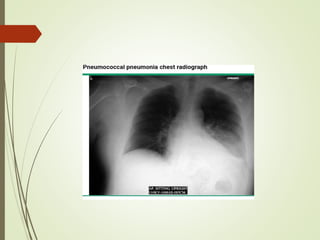

 Chest xray

Diagnostic approach  Chestxray  Sputum examination  Blood culture sensitivity: high risk patient as neutropenic, asplenia,complement deficiency,CLD or severe CAP  Antigen test: for pneumococcal and certain legionella antigen in urine  PCR: detect neucleic acid of legionella spp., M.pneumonia